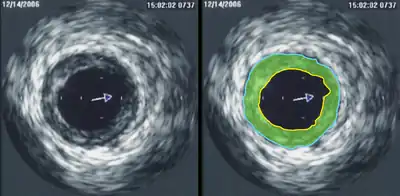

Intravascular ultrasound (IVUS) uses a specially designed catheter with a miniaturized ultrasound probe attached to its distal end, which is then threaded inside a blood vessel. The proximal end of the catheter is attached to computerized ultrasound equipment and allows the application of ultrasound technology, such as a piezoelectric transducer or capacitive micromachined ultrasonic transducer, to visualize the endothelium of blood vessels in living individuals.[11]

A general-purpose ultrasonic transducer may be used for most imaging purposes but some situations may require the use of a specialized transducer. Most ultrasound examination is done using a transducer on the surface of the body, but improved visualization is often possible if a transducer can be placed inside the body. For this purpose, special-use transducers, including transvaginal, endorectal, and transesophageal transducers are commonly employed. At the extreme, very small transducers can be mounted on small diameter catheters and placed within blood vessels to image the walls and disease of those vessels.